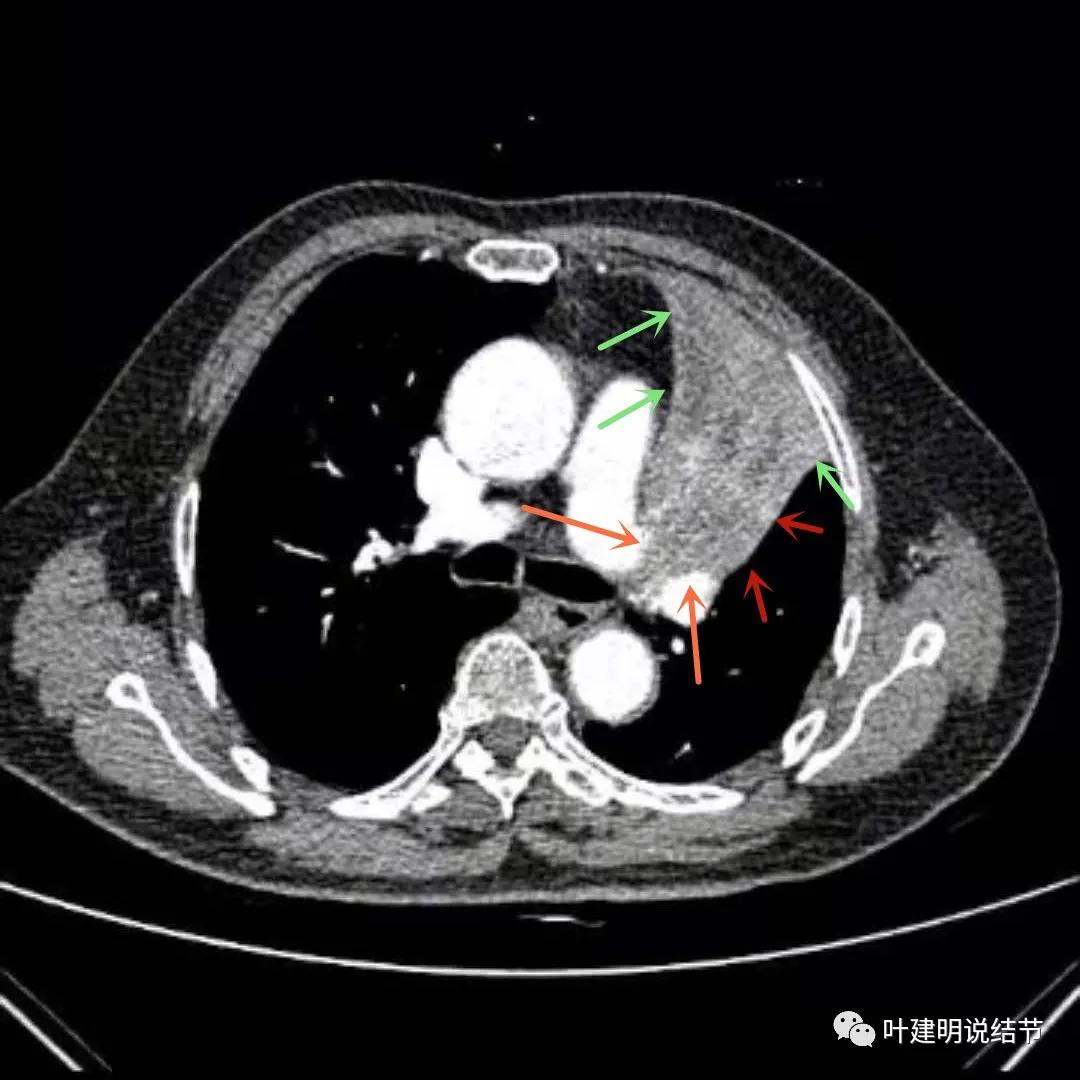

上图绿色箭头所指区域考虑为肺不张,红色示肿瘤处,黄色箭头示肿瘤区域内有坏死低密度,桔色细箭头所指处是被肿瘤包绕的肺动脉分支起始部,粗桔色箭头示肺动脉与肿瘤间紧密愈着,考虑有侵犯肺动脉

上图绿色箭头所指区域考虑为肺不张,红色示肿瘤处且有不均质与膨胀性,桔色细箭头所指处是被肿瘤包绕的肺动脉分支起始部,粗桔色箭头示肺动脉与肿瘤间紧密愈着,考虑有侵犯肺动脉